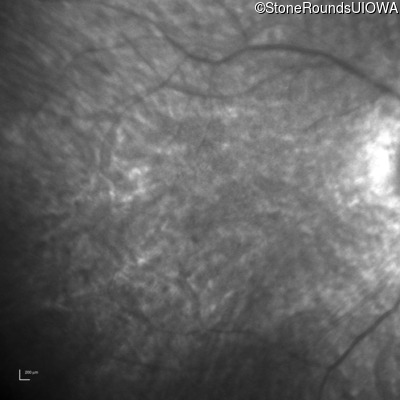

Infrared Fundus Photograph - Right - 20/80 -1

Exemplar

Infrared Fundus Photograph - Left - 20/80